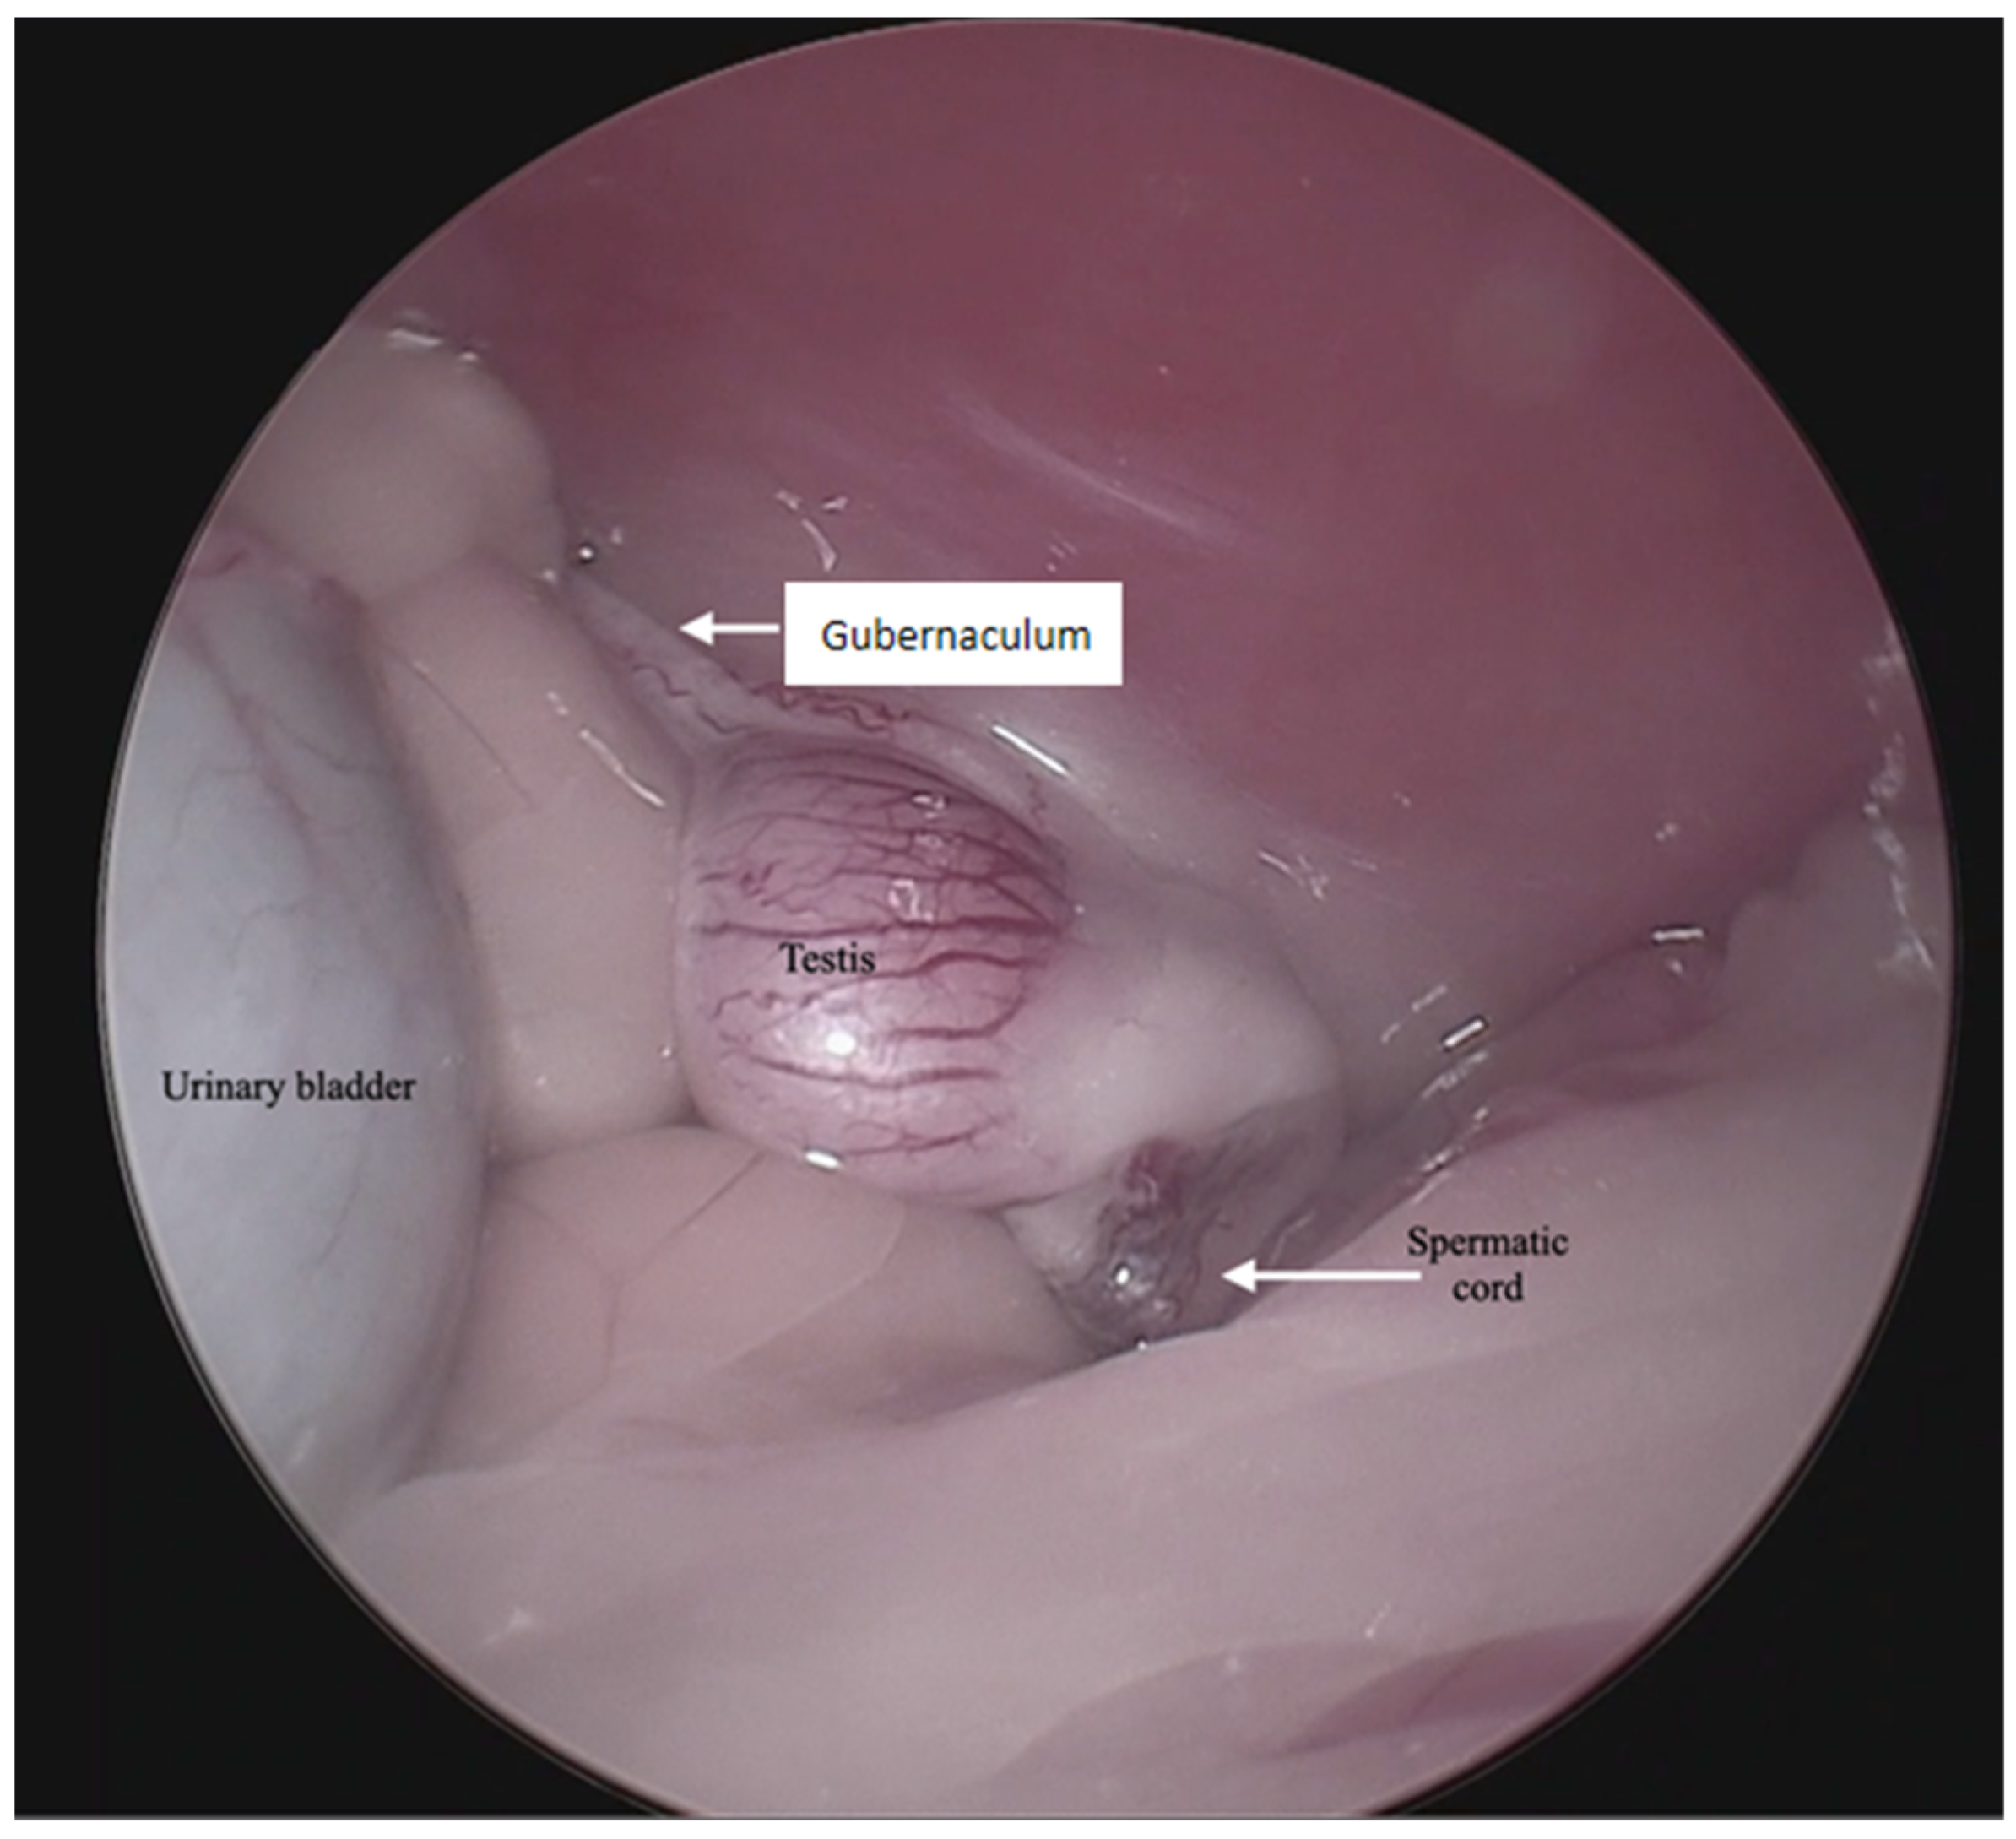

For the surgical procedure, in all cases, inhaled anesthesia was used, and anesthesia monitoring was performed by qualified personnel. In all cases, the main trocar was placed just caudal to the umbilicus using a Hasson technique in 10 cats, modified-Hansson in six cats, and the Veress needle technique in three cats. A small skin incision (<10 mm) was made at this site, and subcutaneous tissues were dissected to visualize the external rectus abdominis sheath; a small stab incision was made into the peritoneal cavity. In 16 cats, a 5 mm trocar was inserted through the incision, and a 6 mm trocar into the remaining 3 cats. The capnoperitoneum was achieved at a rate of 1–2 L/min to an intrabdominal pressure of 7–9 mmHg. A rigid 5 mm telescope with 0° or 30° angle vision was inserted through the trocar, and the abdomen was explored systematically. When an abdominally retained testes was detected, a second access port with a 5 or 6 mm trocar was inserted in a caudal position and slightly lateral to the retained testis, and particularly in the case of the three bilaterally cryptorchid cats, the second trocar was inserted in the center of the caudal abdomen. The second trocar placement was performed with the use of direct visualization through the laparoscope, and transillumination of the abdominal wall was used to avoid blood vessels. To be able to work with two trocars, external suture was used to suspend the testis. The size of the needle was dependent on the size of the animal but had a curvature and sufficient length to allow comfortable entry and exit through the abdominal wall. In the current clinical cases, a 3/8 circle reverse cutting needle ranging from 24 to 30 mm length was commonly used. With transillumination, the most appropriate place to insert the needle was located, avoiding vascularized areas. First, the needle was passed through the abdominal wall, under direct endoscopic visualization and then passed through the testis carefully avoiding vascular structures, and ultimately pulling the needle out through the abdominal wall again. The suture was secured externally with the help of a hemostat, thus fixing the testis to the abdominal wall. In three cases, a percutaneous grasping technique was performed using an open-loop grasper that allowed the testis to be fixed to the abdominal wall with a single puncture; and in three cases, a third port was implemented with two paramedian trocars. With these maneuvers, the detailed visualization of the vascular pedicle, the spermatic cord, and the gubernaculum was achieved (Figure 1 and Figure 2).

Figure 1.

Endoscopic image of the aspect of an intra-abdominal testis.